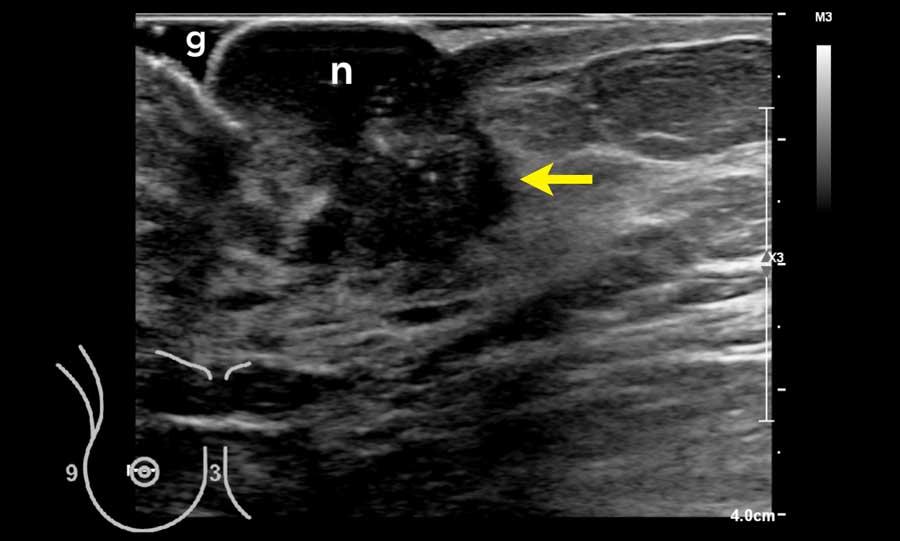

Bệnh nhân này có núm vú lớn, khiến việc khảo sát vùng phía sau núm vú trở nên khó khăn.

Một lượng lớn gel (g) đã được sử dụng để đảm bảo tiếp xúc tốt với da.

Quan sát thấy một khối u lớn phía sau núm vú.